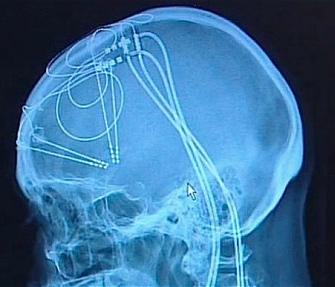

Mulher britânica que sofreu por quase uma década de depressão aguda conseguiu conter o problema graças a uma cirurgia pioneira realizada por uma equipe de pesquisadores da Universidade de Bristol. A depressão levou Sheila Cook, de 62 anos, a se aposentar precocemente e a deixou incapaz de se vestir ou de se alimentar sozinha. Pensamentos sobre suicídio passaram a ser frequentes. Mas a operação realizada no hospital Frenchay, em Bristol, restaurou sua vontade de viver. A técnica, chamada de estimulação cerebral profunda, envolve o uso de fios e eletrodos implantados no cérebro por meio de furos abertos no crânio. Os eletrodos são ligados a uma bateria que envia pequenas quantidades de eletricidade para estimular ou inibir o funcionamento de áreas específicas do cérebro, responsáveis pelo controle das emoções. Os pesquisadores estão analisando os efeitos em duas áreas diferentes do cérebro com oito pacientes. Sheila Cook foi a primeira a passar pela operação, com bons resultados iniciais. “Eu somente queria que a vida terminasse. Era como estar em um túnel escuro, mas em vez de luz no fim do túnel, havia apenas escuridão”, disse ela. “De repente acordei uma manhã e vi que me sentia diferente, queria me levantar e fazer coisas. Minha visão sobre a vida mudou completamente”, completou. Apesar da melhora inicial, Cook teve uma recaída posterior e acabou passando por uma operação mais radical, numa técnica também pioneira em que uma área do cérebro foi danificada para inibir seu funcionamento. Mas os pesquisadores esperam desenvolver a técnica de estimulação cerebral profunda para que ela tenha efeito duradouro ou definitivo e evite a necessidade de novas operações, como no caso de Cook.